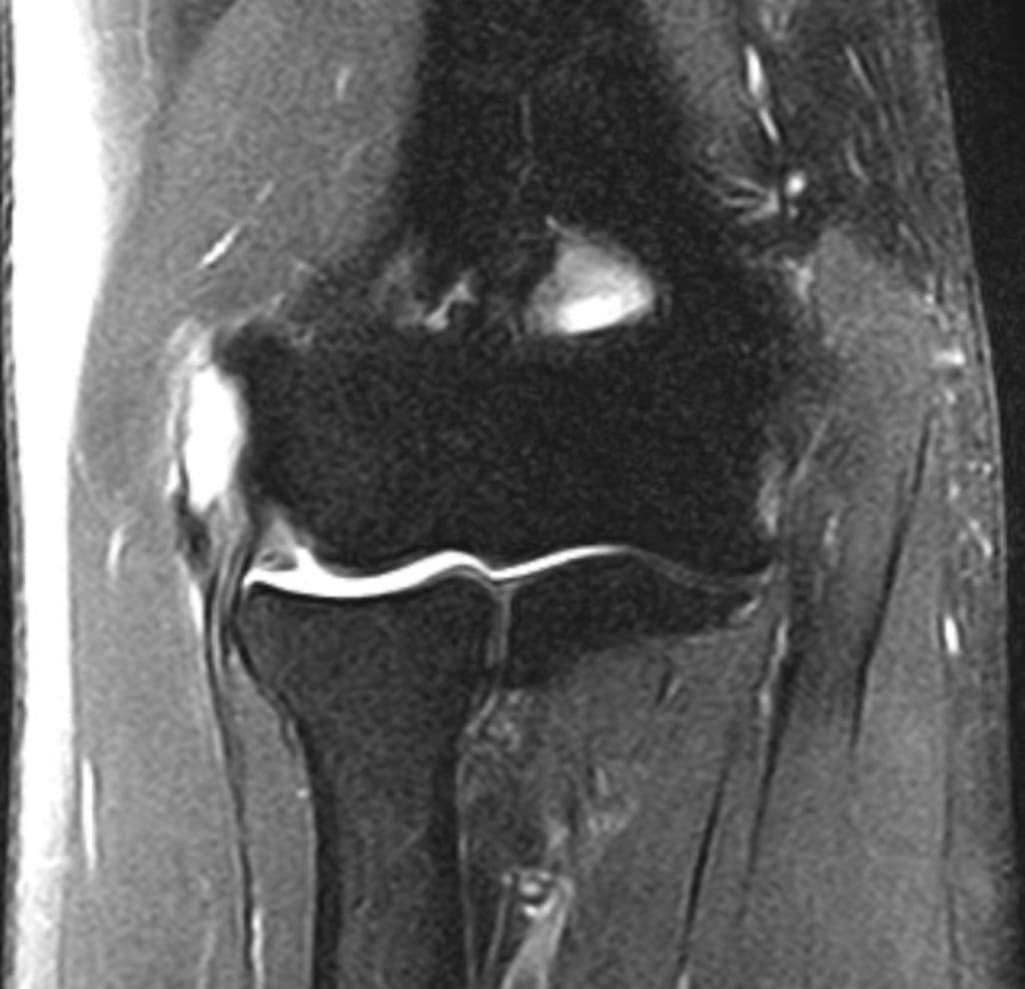

팔꿈치mri인데 수술이 필요한 정도 일까요?

오른쪽 팔꿈치 입니다

사진상으로 많은걸확인할수는없지만 통증과불편감이 5년넘게 지속되었다면 수술을받아보는것도 좋은생각인데요

팔꿈치 질환은 파열 범위 관절 손상 정도에 따라 수술 필요성이 달라져요 5년간 보존치료 후 통증이 악화됐다면 영상 소견에 따라 수술 권유가 나올 수 있습니다.

통증이 5년이상 장기적으로 지속되신 경우, MRI는 주치의가 촬영 검사에서 보이는 손상범위를 종합하여 판단하고 보존적인 치료를 지속하셔도 큰 호전이 없는 경우에는 수술을 고려하실 수 있는데요,

올려주신 사진으로는 질문자분의 증상과 이전 자효와 비교하는 등의 종합적으로 판단하기 어렵기 때문에

MRI 사진 한 컷만으로는 알 수 없습니다.